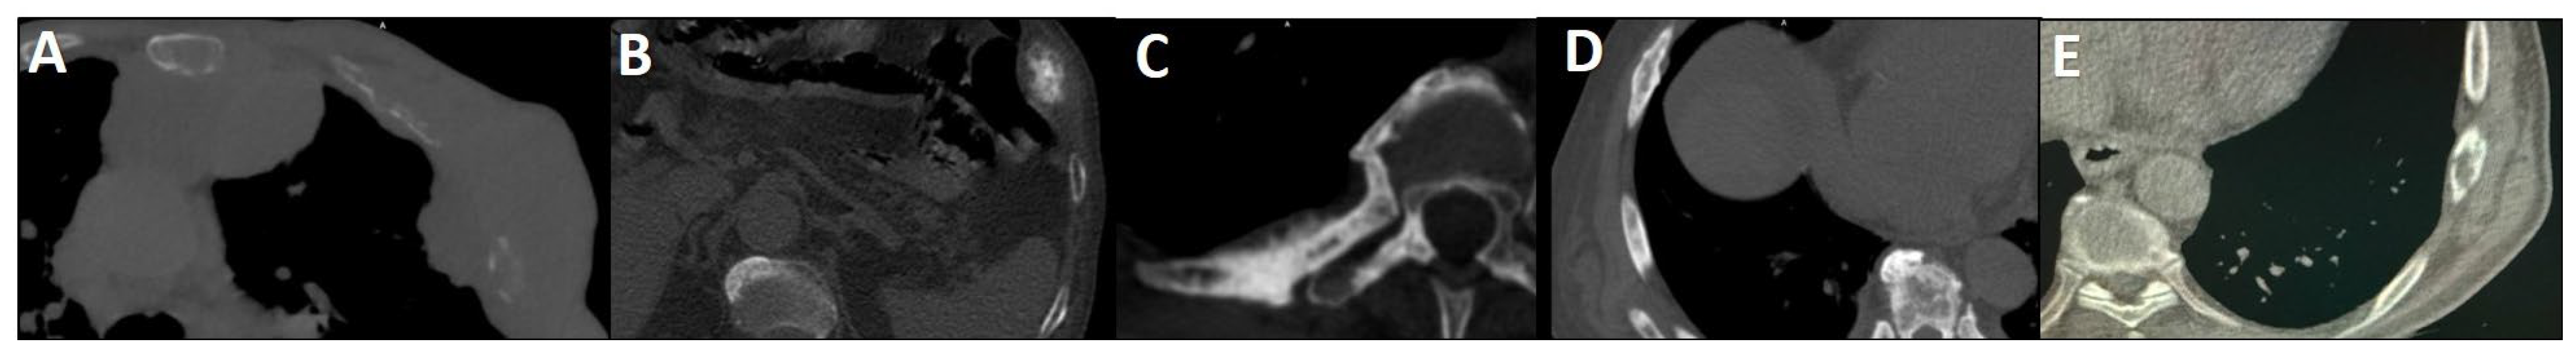

Figure 1.

Spectrum of CT changes in prostate cancer patients, arranged by highest risk of malignancy (A–E). Expansile lytic-destructive lesion with a “soft tissue component”, indicating aggressive variant prostate cancer or concurrent malignancy (A). Sclerotic-destructive metastases with “cortical expansion” (B). Sclerotic metastases showing sun-burst “periosteal reaction” and pathological fracture (C). Sclerotic metastases with “cortical thickening and irregularity” (D). Lytic–sclerotic metastasis featuring “focal small areas of cortical erosion/destruction” (E).